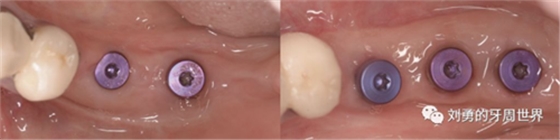

下面這個是我使用國產(chǎn)的替代品的病例:

上圖中,種植體唇側(cè)缺乏附著齦,從上腭取瓣,常規(guī)做法:取長而寬的齦瓣,這樣供區(qū)面積大,術(shù)后疼痛重。

為了減少痛感,從雙側(cè)上腭取多條長而窄的齦瓣進(jìn)行移植,這樣每個供區(qū)的傷口都比較窄,可以減少術(shù)后的痛感。

可見右上前牙植體頰側(cè)無附著齦

為了減少取瓣大小,從上腭取厚一點的齦瓣,然后用刀片平行于表皮表面將齦瓣片切成兩個厚度一致的齦瓣,然后進(jìn)行移植,這樣切成的兩個齦瓣一個有表皮,一個沒有表皮是單純的結(jié)締組織。如此的片切可以使齦瓣變成雙倍的大小使用,減少了供區(qū)的取瓣面積。